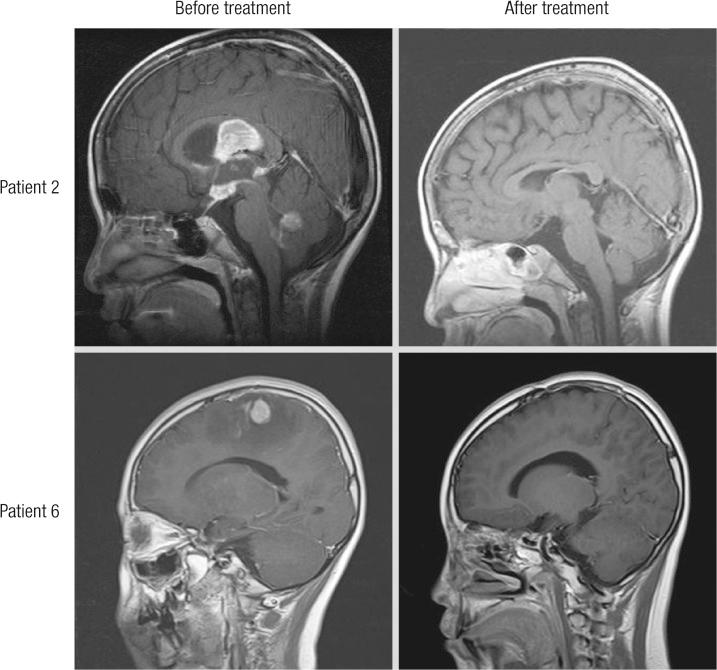

Primary CNS lymphoma (PCNSL) is a very uncommon disease in children, and usually treated by chemotherapy, combined with focal or craniospinal radiotherapy (RT). However, adverse effects of RT are a concern. We evaluated the outcomes of childhood PCNSL, treated with systemic and intrathecal chemotherapy, but without RT. For fifteen years, six patients among 175 of non-Hodgkin lymphoma were diagnosed as PCNSL in Seoul National University Children's Hospital and we analyzed their medical records retrospectively. Their male:female ratio was 5:1, and median age was 10.1 yr. The primary sites were the sellar area in three patients, parietal area in one, cerebellum in one, and multiple areas in one. Their pathologic diagnoses were diffuse large B-cell lymphoma in three patients, Burkitt lymphoma in two, and undifferentiated B-cell lymphoma in one. Five were treated with the LMB96 treatment protocol, and one was treated with the CCG-106B protocol. None had RT as a first-line treatment. One patient had a local relapse and received RT and salvage chemotherapy, without success. No patient had treatment-related mortality. Their estimated 5-yr event-free and overall survival rates were both 83.3%. In conclusion, PCNSL is a rare disease in childhood, but successfully treated by chemotherapy without RT.

原发性中枢神经系统淋巴瘤(PCNSL)在儿童中非常罕见,通常采用化疗联合局部或全脑脊髓放疗(RT)治疗。然而,RT 的不良反应令人担忧。我们评估了 175 例非霍奇金淋巴瘤患儿中,6 例接受全身和鞘内化疗而未接受 RT 治疗的 PCNSL 患儿的结局。在首尔国立大学儿童医院,15 年来,175 例非霍奇金淋巴瘤患儿中有 6 例被诊断为 PCNSL,我们对这些患儿的病历进行了回顾性分析。患儿的男女比例为 5:1,中位年龄为 10.1 岁。3 例患儿的原发部位为鞍区,1 例为顶叶,1 例为小脑,1 例为多部位。3 例患儿的病理诊断为弥漫性大 B 细胞淋巴瘤,2 例为伯基特淋巴瘤,1 例为未分化 B 细胞淋巴瘤。5 例患儿接受 LMB96 治疗方案,1 例患儿接受 CCG-106B 方案治疗。所有患儿均未将 RT 作为一线治疗。1 例患儿局部复发,接受 RT 和挽救化疗,但未成功。无患儿因治疗相关死亡。患儿的 5 年无事件生存率和总生存率均为 83.3%。总之,PCNSL 在儿童中较为罕见,但可通过化疗而非 RT 成功治疗。